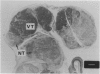

Experimental studies have been carried out using 5-aminolaevulinic acid (ALA) to induce transient porphyrin photosensitisation for photodynamic therapy (PDT) in a pancreatic cancer model in Syrian golden hamsters. ALA was given either intravenously or orally (in bolus or fractionated doses) with the laser light delivered by means of a bare fibre touching the tissue surface or external irradiation using a light-integrating cylindrical applicator. Animals were killed 1-24 h after ALA administration for pharmacokinetic studies and 3-7 days after light exposure to study PDT-induced necrosis. A separate survival study was also performed after a fractionated oral dose of ALA and external irradiation. Protoporphyrin IX sensitisation in the tumour tissue as measured by quantitative fluorescence microscopy was highest after intravenous administration of 200 mg kg-1 ALA and then in decreasing order after oral fractionated and oral bolus doses (both 400 mg kg-1). Laser light application at 630 nm to give 12-50 J from the bare fibre or 50 J cm-2 using surface illumination with the cylindrical applicator resulted in tumour necrosis up to 8 mm in depth. In larger tumours a rim of viable tumour was observed on the side opposite to illumination. In a randomised study, survival of treated animals was significantly longer than in the untreated control group (log-rank test, P < 0.02), although all animals died of recurrent tumour. This technique shows promise in the treatment of small volumes of tumour in the pancreas.